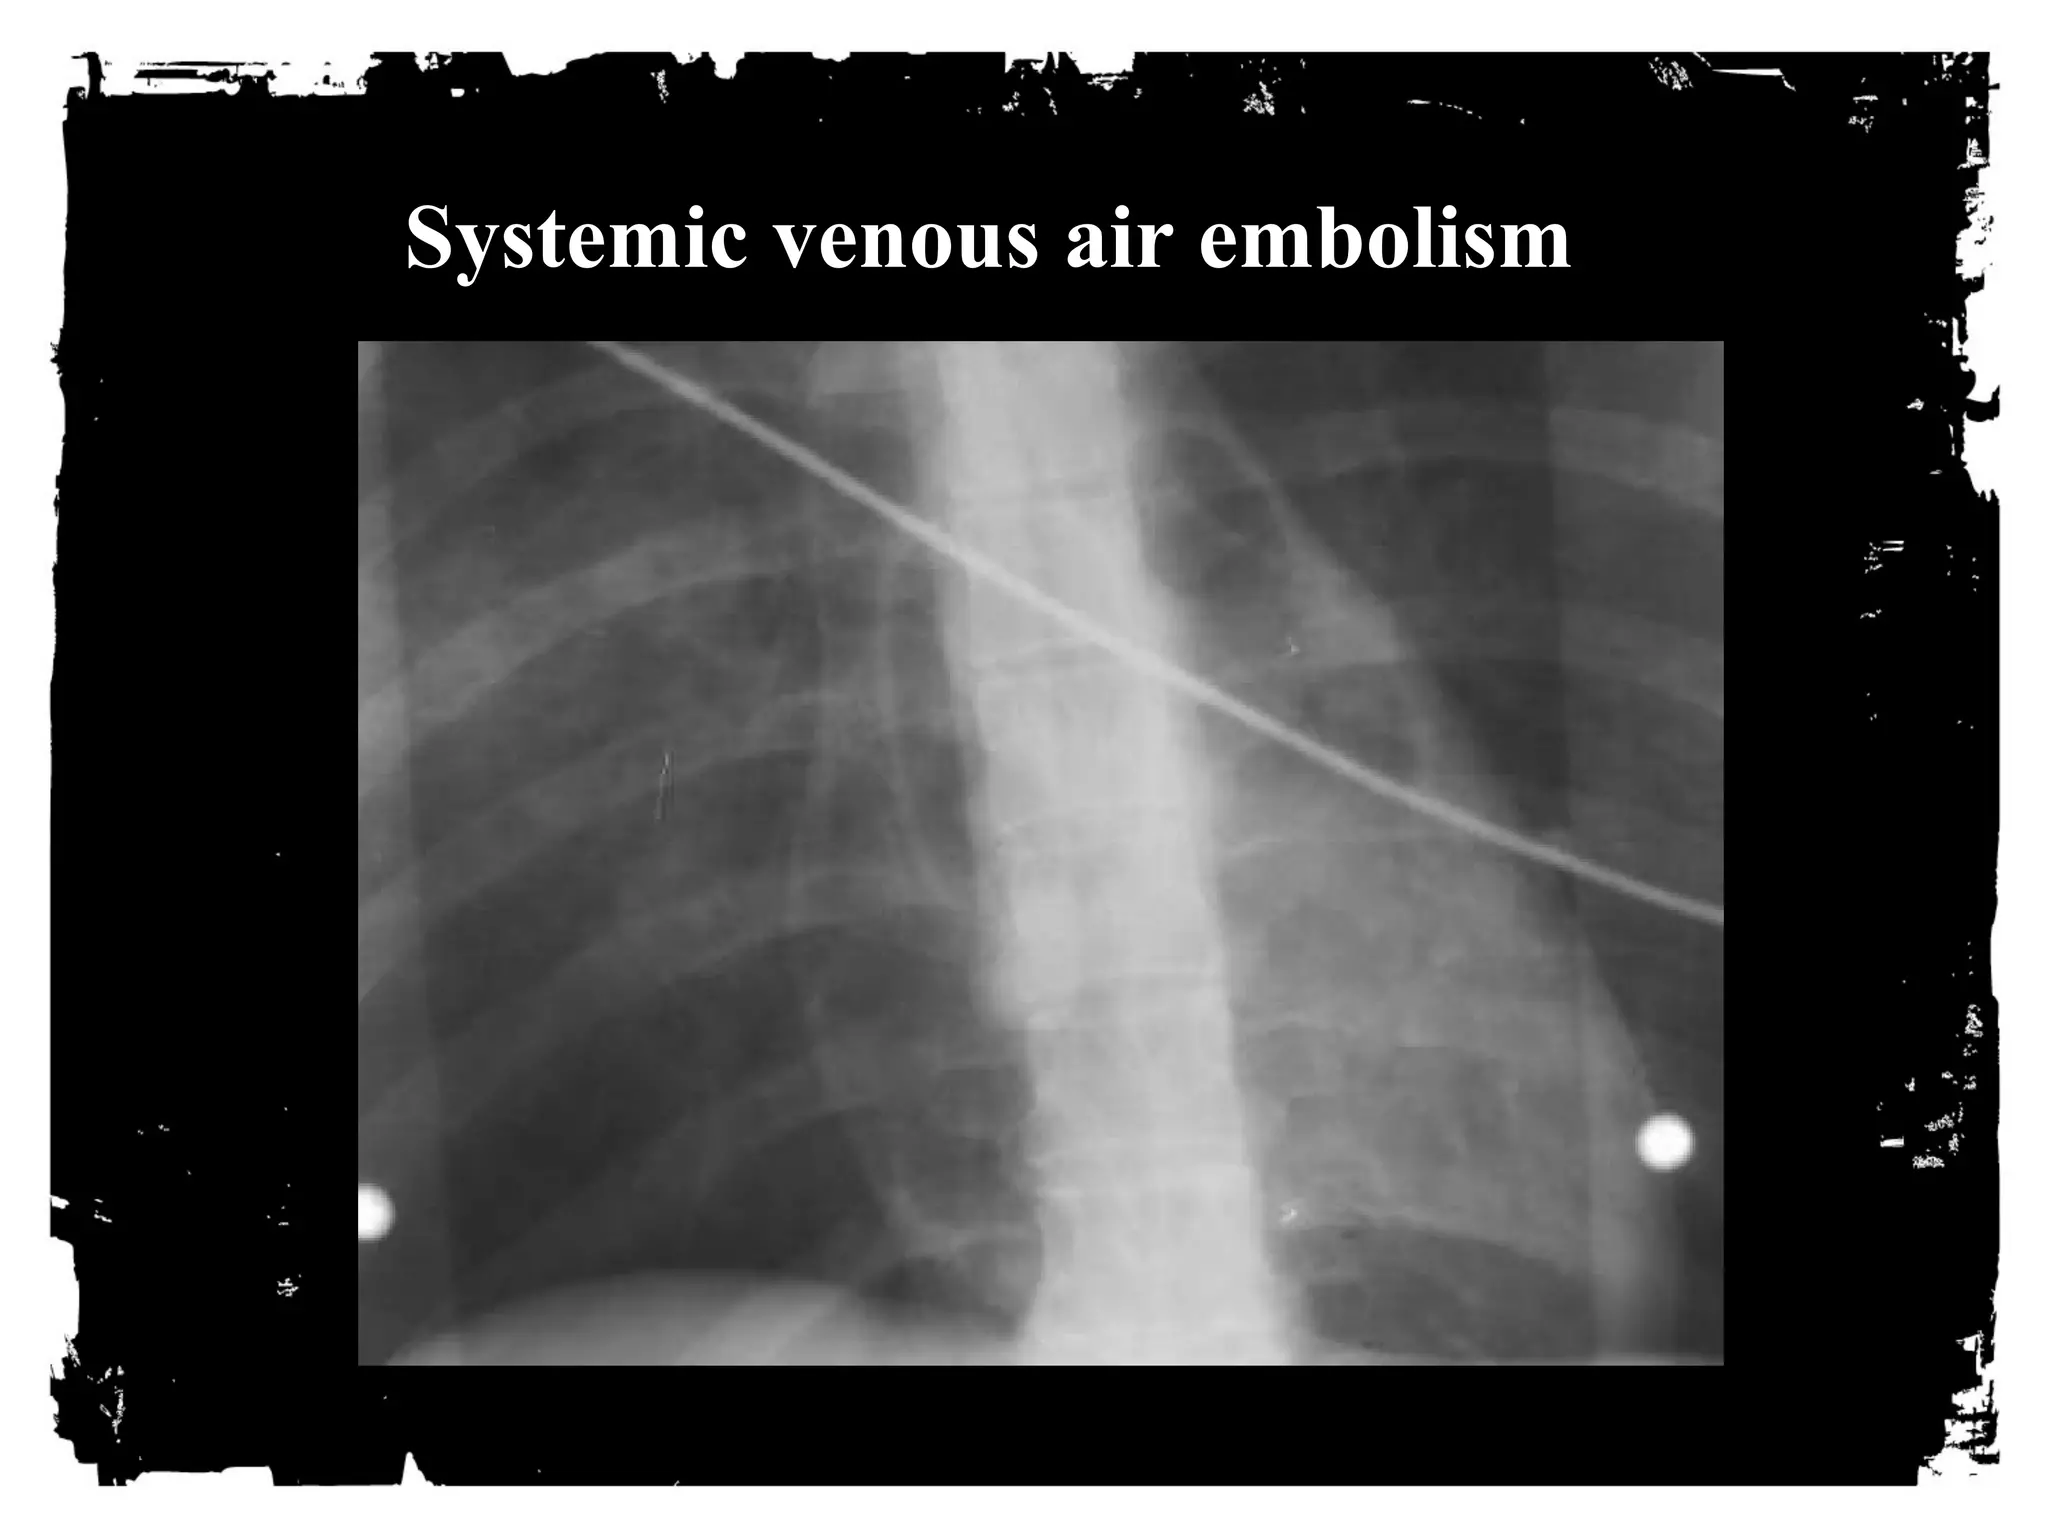

AIR where it shouldn’t be

• Pneumothorax

• Pneumomediastinum

• Subcutaneous emphysema

• Systemic venous air embolism

• Pneumopericardium

• Pneumoperitoneum/retroperitoneum

Systemic venous air embolism